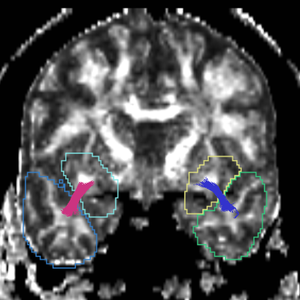

Region

caseD00917

caseD00920

caseD00924

caseD00928

caseD00935

caseD00936

caseD00938

caseD00939

caseD00940

Uncinate Fasciculus

Internal Capsule

Fornix

Cingulum

Arcuate Fasciculus